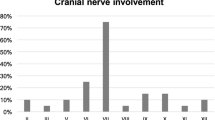

Patients can present with subtle and non-specific symptoms as persistent headache and eventual development of cranial neuropathy [9•]. However, most patients present with unrelenting otalgia that is disproportional to the clinical signs. There can be persistent purulent otorrhea, with an intact tympanic membrane and usually intact hearing. Otological examination may reveal oedema of the external auditory canal (EAC) and the presence of granulation tissue or polyp of the EAC floor near the junction of the osseous and cartilaginous portions [1•, 10]. The granulation tissue can be caused by the underlying osteitis. Patients can present with cranial nerve deficits, which can be caused by necrosis, neurotoxins and compression. Non-responsiveness to therapy is considered an important criterion in literature for the diagnosis of MOE [10].

The spread along the temporal bone through the fissures of Santorini commonly involves the styloid mastoid foramen (containing the facial nerve) and the jugular foramen (containing the glossopharyngeal, vagal and accessory nerves) [3]. Subtemporal extension starts at the osteocartilaginous junction, near the fissure of Santorini and spreads to the retrocondylar fat, the parapharyngeal fat, temporomandibular joint and masticator muscles.

The prognosis of SBO has improved significantly with adequate antimicrobial therapy. Patients are more likely to have remitting disease or higher mortality rates show a more extensive infectious spread of SBO such as bilateral disease, involvement of the temporomandibular joint, infratemporal fossa or soft tissues of the nasopharynx [15]. The prognostic value of cranial nerve involvement such as the facial nerve remains unclear as some studies find an association with an increased mortality rate, while others dismiss this association [4, 15]. Overall, the survival for elderly patients is lower in comparison with younger patients, partially due to associated comorbidity. However, there is a higher morbidity rate than to be expected for the elderly with a significant age-related decline in survival. Patients above 70 year of age have a 5 year survival of 44%, in contrast to patients under 70 years with a 5-year survival rate of 75% [15].